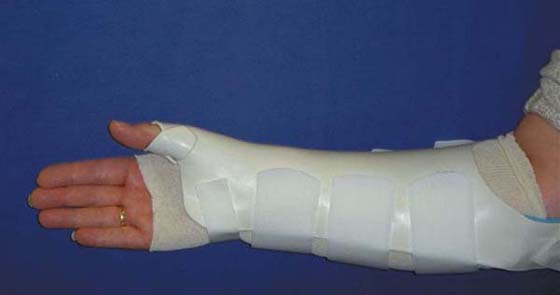

Alternative Immobilization of the Wrist

Lengthy periods of wrist immobilization may lead to stiffness, pain, and weakness. Skirven developed an alternative orthosis to allow for limited postoperative wrist motion. This flexible wrist orthosis was described in 1989 by Bora and colleagues59 for use after scaphoid fracture (Fig. 76-12). They proposed the following benefits over complete immobilization: (1) control and preservation of short-arc wrist motion, (2) decreased bone osteopenia, (3) maintenance of articular cartilage health, (4) stimulation of healing, and (5) increased independence in the performance of ADLs. The orthosis allows approximately 30 degrees of a wrist flexion–extension arc of motion, limits ulnar and radial deviation, and at rest provides support and stability. This orthosis may be used after intercarpal fusions, after an appropriate time period of postoperative casting, when there is radiographic evidence of healing, and with a reliable patient. It is worn full time and removed only for hygiene.

images

Figure 76-12 A flexible wrist orthosis may be used postoperatively for limited and controlled wrist motion.